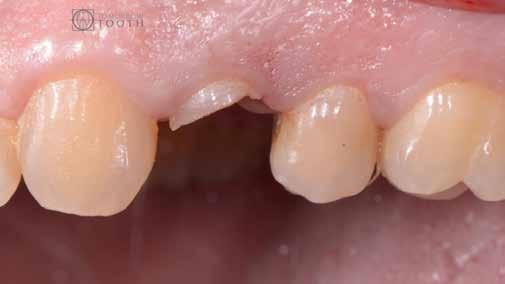

Egy 35 éves kaukázusi férfi páciens az 1.4-es fog (felső első premoláris) törése miatt kereste fel rendelőnket, a törés ferde volt. A sérült fogak helyreállítása során az egyik legfontosabb lépés a megmaradt fogazat biomechanikai értékelése . Egy hiba ebben a fázisban káros a hosszú távú eredményre . A legtöbb repedést például a fogüregek helyreállító fogászathoz való helytelen előkészítése okozza. Ugyanígy a fennmaradó szerkezet helytelen értékelése idővel mechanikai okokból bekövetkező meghibásodáshoz vezethet.

2. ábra: Az okkluzális nézet a fogszerkezet mennyiségét mutatja, a röntgenfelvételen az 1.5. fogon II. osztályú szuvasodás is látható. Még ha lehetséges is ezeket az eseteket koronahosszabbítással kezelni, a végeredmény átlagosan nem kielégítő. A ferrule gyógyulása korlátozott, és olyan parodontális szövődményekkel is találkozunk, mint a fekete háromszögek, a szomszédos fogak gyökérkitettsége. A fogszabályozó extrúzió sokkal előnyösebb.